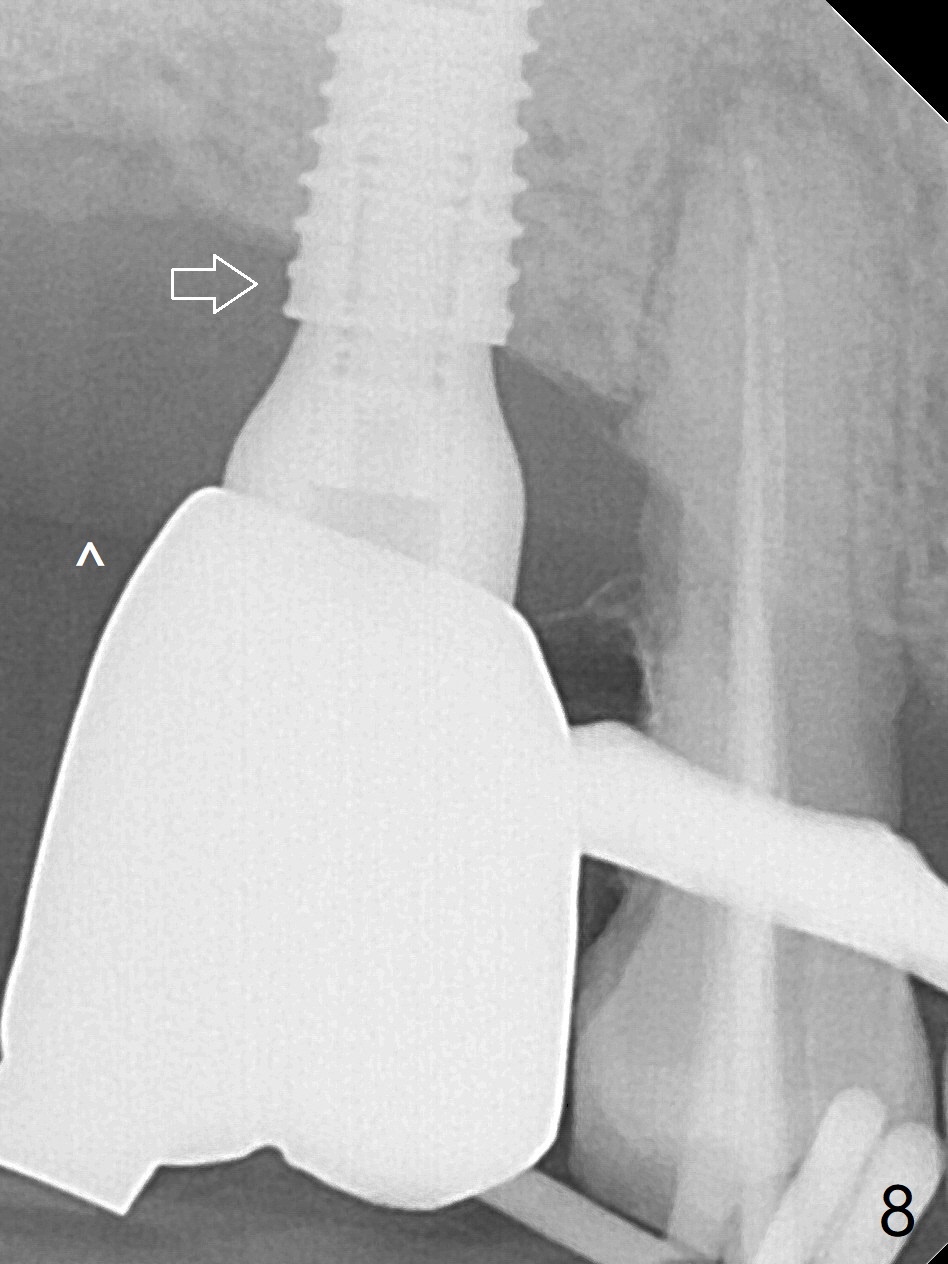

Since the ridge crest at #3 is narrow, Tatum bone scalpels are used to get access and initiate bone expansion, followed by bone blades and RT 2. It seems that the osteotomy starts mesially; bone height being increased (Fig.1). When the apical end of the osteotomy tilts mesially, more bone height is obtained. Drills are alternatively applied because of the hard bone (Fig.2). A 4x13 mm UF implant is placed initially with the distal threads unburied (Fig.3, >50 Ncm). With further seating of the implant, a 5.5x5(4) mm abutment is used (Fig.4), which closes the access. No suture is warranted. An immediate provisional is fabricated for the patient's comfort and psychological effect. In fact, the abutment cuff changes to 5 mm prior to temporarization. There appears no bone loss <4 months postop (Fig.5). Pulpitis develops at #4 due to DO caries 1 year 5 months post cementation (Fig.6 *). The crown at #3 is removed for easy and conservative distal carious removal and Cavit temporary restoration to prevent sodium hypochlorite leakage. Then occlusal access is made for pulpotomy. When RCT finishes, no crown will be made, but occlusal reduction is required. The patient returns for RCT 1 month later (Fig.7,8). Cavit remains in place (Fig.7 C). Although 2 threads are exposed distal (Fig.8 arrow), there is no sign or symptom of periimplantitis, which may be related to the thick gingiva (arrowhead). Return to Upper Molar Immediate Implant, IBS, #14 (Tissue Punch) Xin Wei, DDS, PhD, MS 1st edition 08/25/2017, last revision 09/08/2019